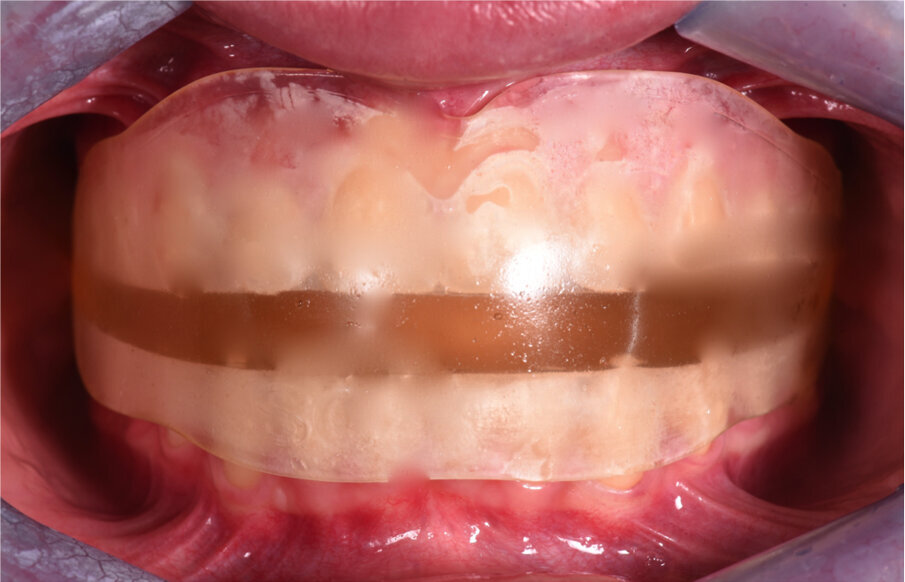

Analisi dei dispositivi funzionali Elastodontici Il trattamento con il Bio-Attivatore A.M.C.O.P. by Micerium è sorprendentemente semplice, naturale, innovativo e non invasivo e può essere considerato una straordinaria bio-ortopedia oro-cranio-facciale. È infatti un dispositivo ortodontico elastico di grande validità terapeutica di carattere funzionale, specificatamente ortopedico del sistema dento-cranio-facciale.

È un armonizzatore delle distorsioni simultanee delle basi scheletriche mascellari e mandibolari ed è adatto per il livellamento dei piani occlusali inclinati, ruotati e torsionati per una corretta funzione ed un buon equilibrio della bocca. Il dispositivo è anche un validissimo strumento di lavoro decontratturante, detensionale di diverse problematiche muscolo-tensive e si rivela molto indicato anche per la riabilitazione delle articolazioni temporo-mandibolari (ATM). Se correttamente utilizzato, è in grado di procurare processi antinfiammatori e riparativi determinanti che vanno al di là di semplici trattamenti occlusali che danno al paziente l’opportunità di rimediare scompensi di carattere sintomatico e quindi psicologico.

L’azione riabilitativa del Bio-Attivatore si riflette su tutto il sistema stomatognatico: denti, alveoli, muscoli masticatori, ATM, guance, labbra, lingua, tessuti molli, ghiandole salivari, ossa mandibolari e mascellari, innervazione e vascolarizzazione e quindi il sistema dento-craniofacciale e cervico-posturale. Corregge, quindi, le abitudini viziate e i dismorfismi cranio-facciali, vere cause delle malocclusioni.

Il dispositivo è anche consigliato a pazienti con bruxismo e russamento notturno.

I Bio-Attivatori A.M.C.O.P. by Micerium costituiscono la sintesi di tutti gli attivatori funzionali esistenti e sono adatti ad una riabilitazione funzionale e personalizzata del paziente. Essi forniscono una visione più ampia e corretta del trattamento, poiché il dispositivo agisce come crescita armoniosa del sistema dentocranio-facciale e ne stabilizza il risultato ottenuto. La forma nasce per necessità del nostro corpo di espletare una funzione. Il dispositivo è indicato per migliorare le funzioni neurovegetative della bocca, della deglutizione, della masticazione, della fonazione e della respirazione per migliorare la funzione naso-ventilatoria con un ritorno alla normofunzione del distretto naso-oro-laringo-faringeo.

Gli apparecchi elastodontici sono realizzati con un materiale termoplastico in grado di interagire in maniera attiva con l’occlusione, i muscoli della lingua, il muscolo orbicolare ma nello stesso tempo sono in grado di creare un spazio cosiddetto elastodontico il quale rappresenta lo spazio ideale tra la muscolatura della lingua (forza centrifuga) e quelle delle labbra (forza centripeta) all’interno del quale avviene lo spostamento degli elementi dentali; quindi non è l’apparecchio stesso a determinare il movimento dentale ma è l’equilibrio che si instaura tra la muscolatura delle labbra e quella della lingua a creare uno spazio neutro all’interno del quale si posizionano gli elementi dentali stessi.